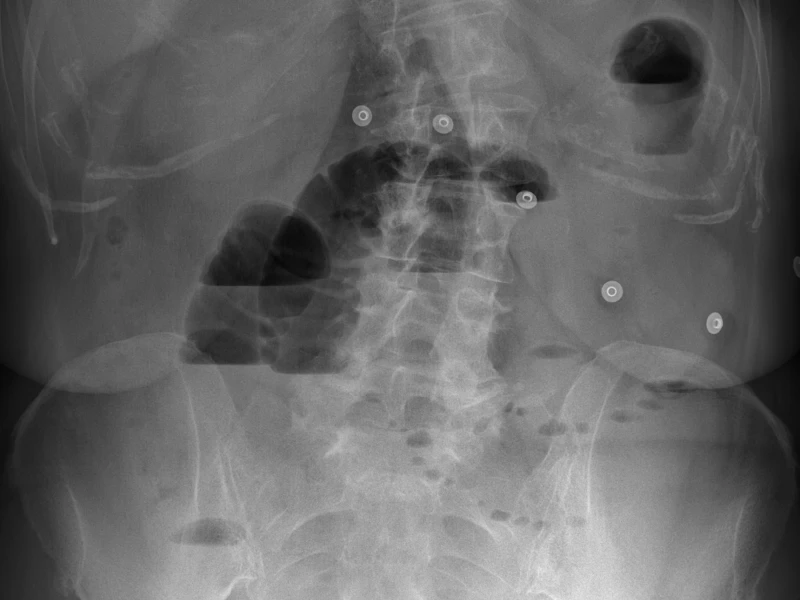

Radiografía de abdomen